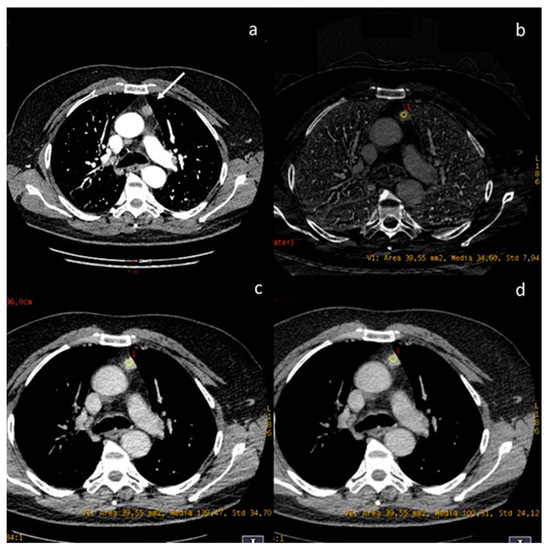

- Li, W.; Liu, M.; Yu, F.; Zhu, W.; Yu, X.; Guo, X.; Yang, Q. Detection of left atrial appendage thrombus by dual-energy computed tomography-derived imaging biomarkers in patients with atrial fibrillation. Front. Cardiovasc. Med. 2022, 9, 809688. [Google Scholar] [CrossRef] [PubMed]